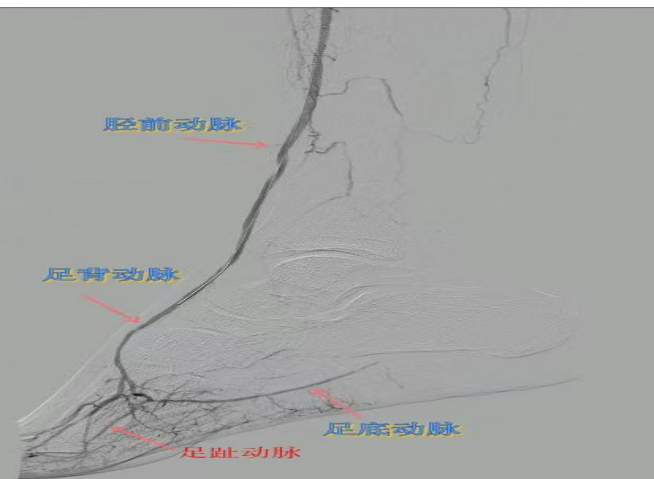

78岁男性患者,糖尿病合并高血压、脑梗塞,右足持续疼痛伴冰凉发绀3个月。入院CTA显示其右侧股浅动脉全程闭塞,膝下三支动脉均闭塞。医疗团队在局部麻醉下,再次巧妙应用“逆向开通技术”,经胫后动脉——足底弓逆向开通足背动脉及胫前动脉。术后患者右足皮温即刻回升,疼痛消失。术后结合中药外治(换药、熏洗、去腐生肌膏外敷)加速创面愈合,患者已顺利出院。

影像检查:CTA显示右侧股浅动脉全程闭塞,膝下三支动脉(胫前、胫后、腓动脉)完全闭塞。